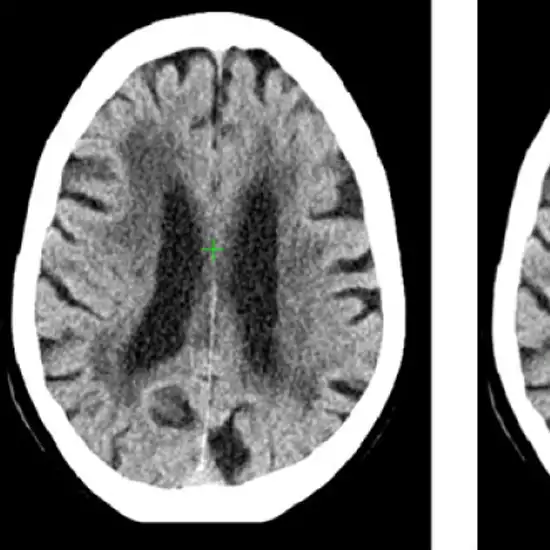

CT Intra Cranial Vessels is a non-invasive imaging scan that is used to detect abnormalities in your brain’s blood vessels. This scan uses a rotating x-ray beam and contrast media to create a detailed picture of the blood vessels of the head and neck.